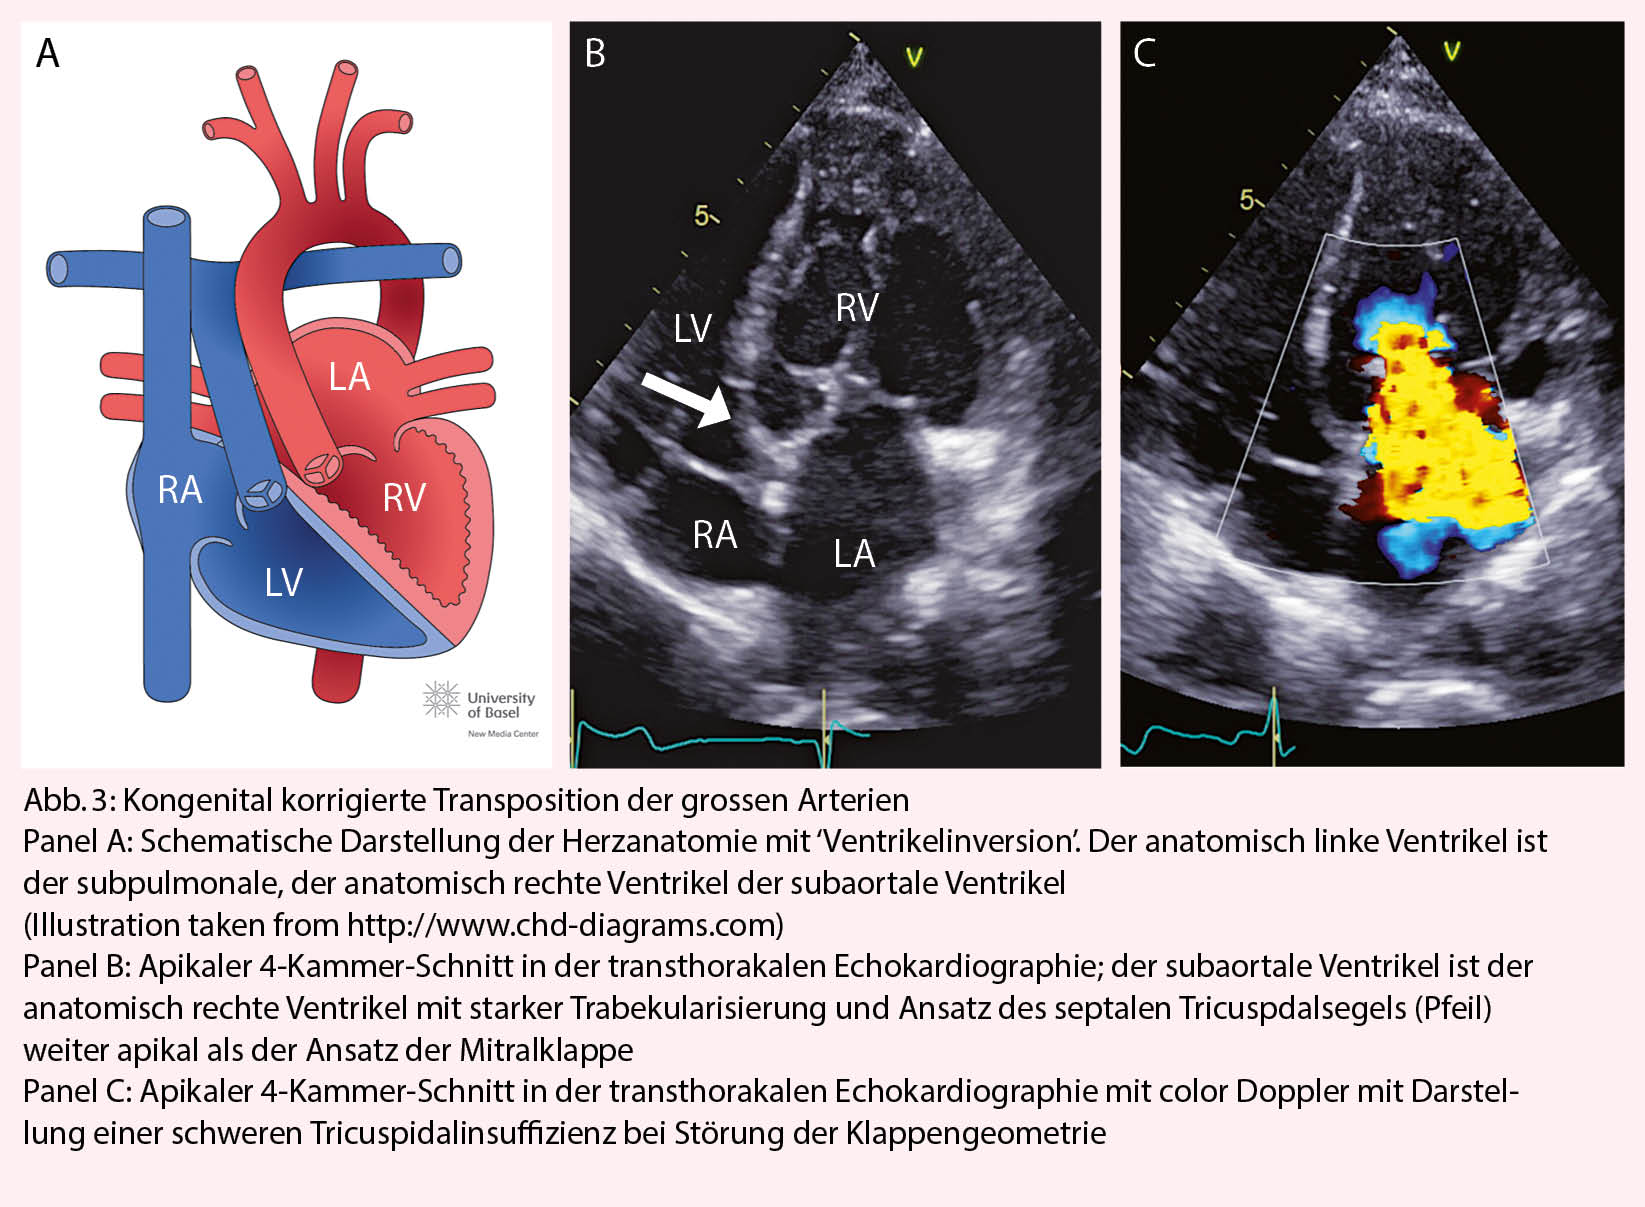

Kongenital korrigierte Transposition der grossen Arterien

Die Ursache der kongenital korrigierten Transposition der grossen Arterien ist eine fehlerhafte ‘Faltung’ des Herzschlauches während der Embryonalentwicklung. Durch den L-loop kommt es physiologisch zur ‘Ventrikelinversion’. Das heisst, der rechte Vorhof konnektiert zum morphologisch linken Ventrikel, der linke Vorhof zum morphologisch rechten Ventrikel. Die Pulmonalarterie entspringt dem subpulmonalen linken, die Aorta dem subaortalen rechten Ventrikel (Abb. 3). Wenn zusätzliche Defekte vorliegen (am häufigsten sind Ventrikelseptumdefekte und die Pulmonalstenose) erfolgt die Diagnose meist im Kindesalter. Bei Fehlen zusätzlicher Defekte wird die Diagnose gelegentlich erst im Erwachsenenalter gestellt. Dann meist bei Auftreten von Komplikationen (progrediente Tricuspidalinsuffizienz, Herzinsuffizienz oder atrioventrikulärer Block). Die Betreuung solcher Patienten sollte in Zusammenarbeit mit einem spezialisierten Zentrum erfolgen.